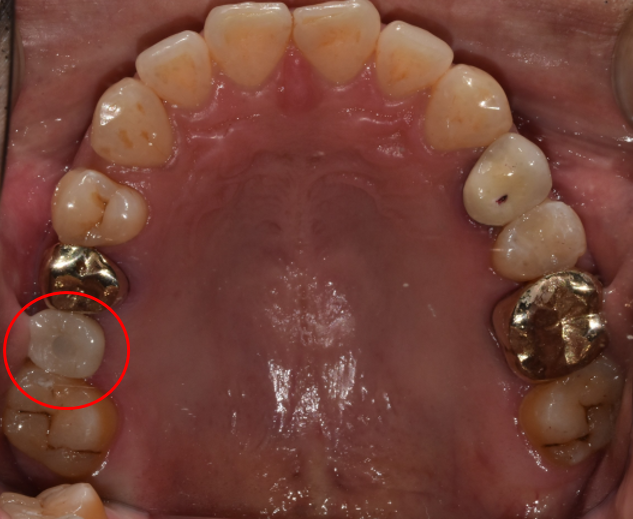

임플란트 전 Before & After

임플란트 시술에는 발치하고 나서 바로 식립하는 방법과 발치하고 얼마 정도 시간이 흐른 다음 식립하는 지연 식립이 있습니다. 바로 식립할 때는 발치하고 기다리는 시간이 없으므로 3개월 만에 치료를 마칠 수 있습니다.

이는 환자분들의 구강건강 상태와 치아 구조를 보고 식립 방법을 결정하게 됩니다. 구강상태가 좋지 않거나 치아가 약하다면 바로 식립하기보다는 지연 식립 방법으로 진행할 수 있습니다.

임플란트 치료는 자연치아와 가장 유사한 모양으로 구현해 내야 합니다. 디데이치과에서는 3D 기법을 활용해 네비게이션 임플란트 방식으로 치료를 도와드리고 있습니다.

다른 시술에 비해 네비게이션 임플란트는 환자 한 분 한 분에게 가장 알맞은 치아 구조 형태를 만들어낸다는 장점을 가지고 있습니다.